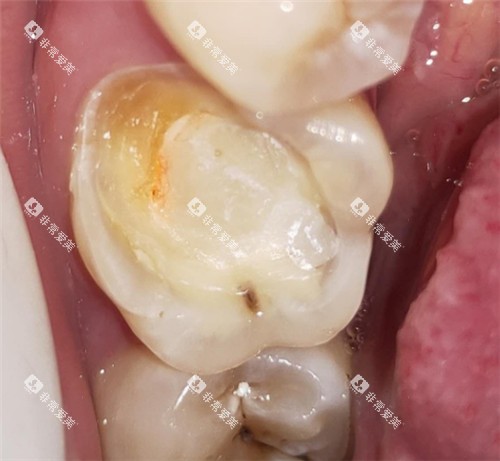

根管治疗主要用于治疗牙髓炎、根尖周炎等牙髓疾病。

在金华地区,根管治疗的收费价格与牙齿的部位和根管数量有关。

前牙的根管数量较少,一般为1 - 2个,根管治疗的费用相对较低,单颗牙齿的根管治疗费用大约在300 - 800元。

前磨牙的根管数量一般为1 - 2个,治疗费用在500 - 1200元左右。

磨牙的根管数量较多,通常为3 - 4个,根管治疗的难度也相对较大,单颗磨牙的根管治疗费用在800 - 2000元不等。

此外,如果根管治疗后需要进行牙冠修复,牙冠的费用也需要另外计算。

不同材料的牙冠价格差异较大,烤瓷牙冠的价格一般在500 - 2000元左右,全瓷牙冠的价格在1500 - 4000元左右。